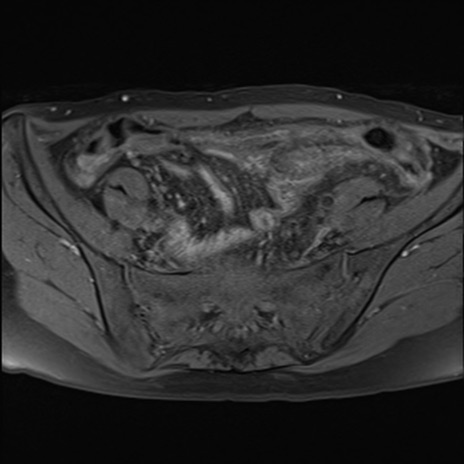

症例39 脂肪抑制T1WI(横断像)

MRI(4日後)

T1WI(横断像)